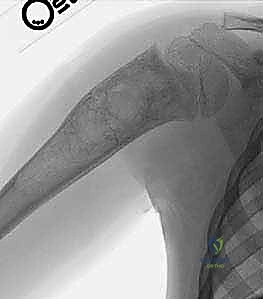

تُظهر هذه الأشعة السينية (X-ray) كيس عظم أحادي الغرفة (UBC) في الجزء العلوي من عظم العضد. لاحظ كيف أن الكيس يسبب ترققاً في قشرة العظم دون أن يخترقها.

- في الـ UBC، تظهر الآفة كمنطقة شفافة (سوداء) مركزية داخل العظم. وهناك علامة مميزة تُسمى "علامة الورقة المتساقطة" (Fallen Leaf Sign)، حيث تسقط قطعة صغيرة من قشرة العظم المكسورة داخل الكيس المملوء بالسائل، وهي علامة مؤكدة بنسبة 100% تقريباً على الـ UBC.

في الـ ABC، تظهر الآفة غير مركزية، متمددة، وتدفع قشرة العظم للخارج لتصبح رقيقة جداً مثل "قشرة البيضة".

تُظهر هذه الأشعة السينية كيس عظم متمدد (ABC). لاحظ التوسع الكبير في العظم وترقق القشرة العظمية مقارنة بالكيس أحادي الغرفة.